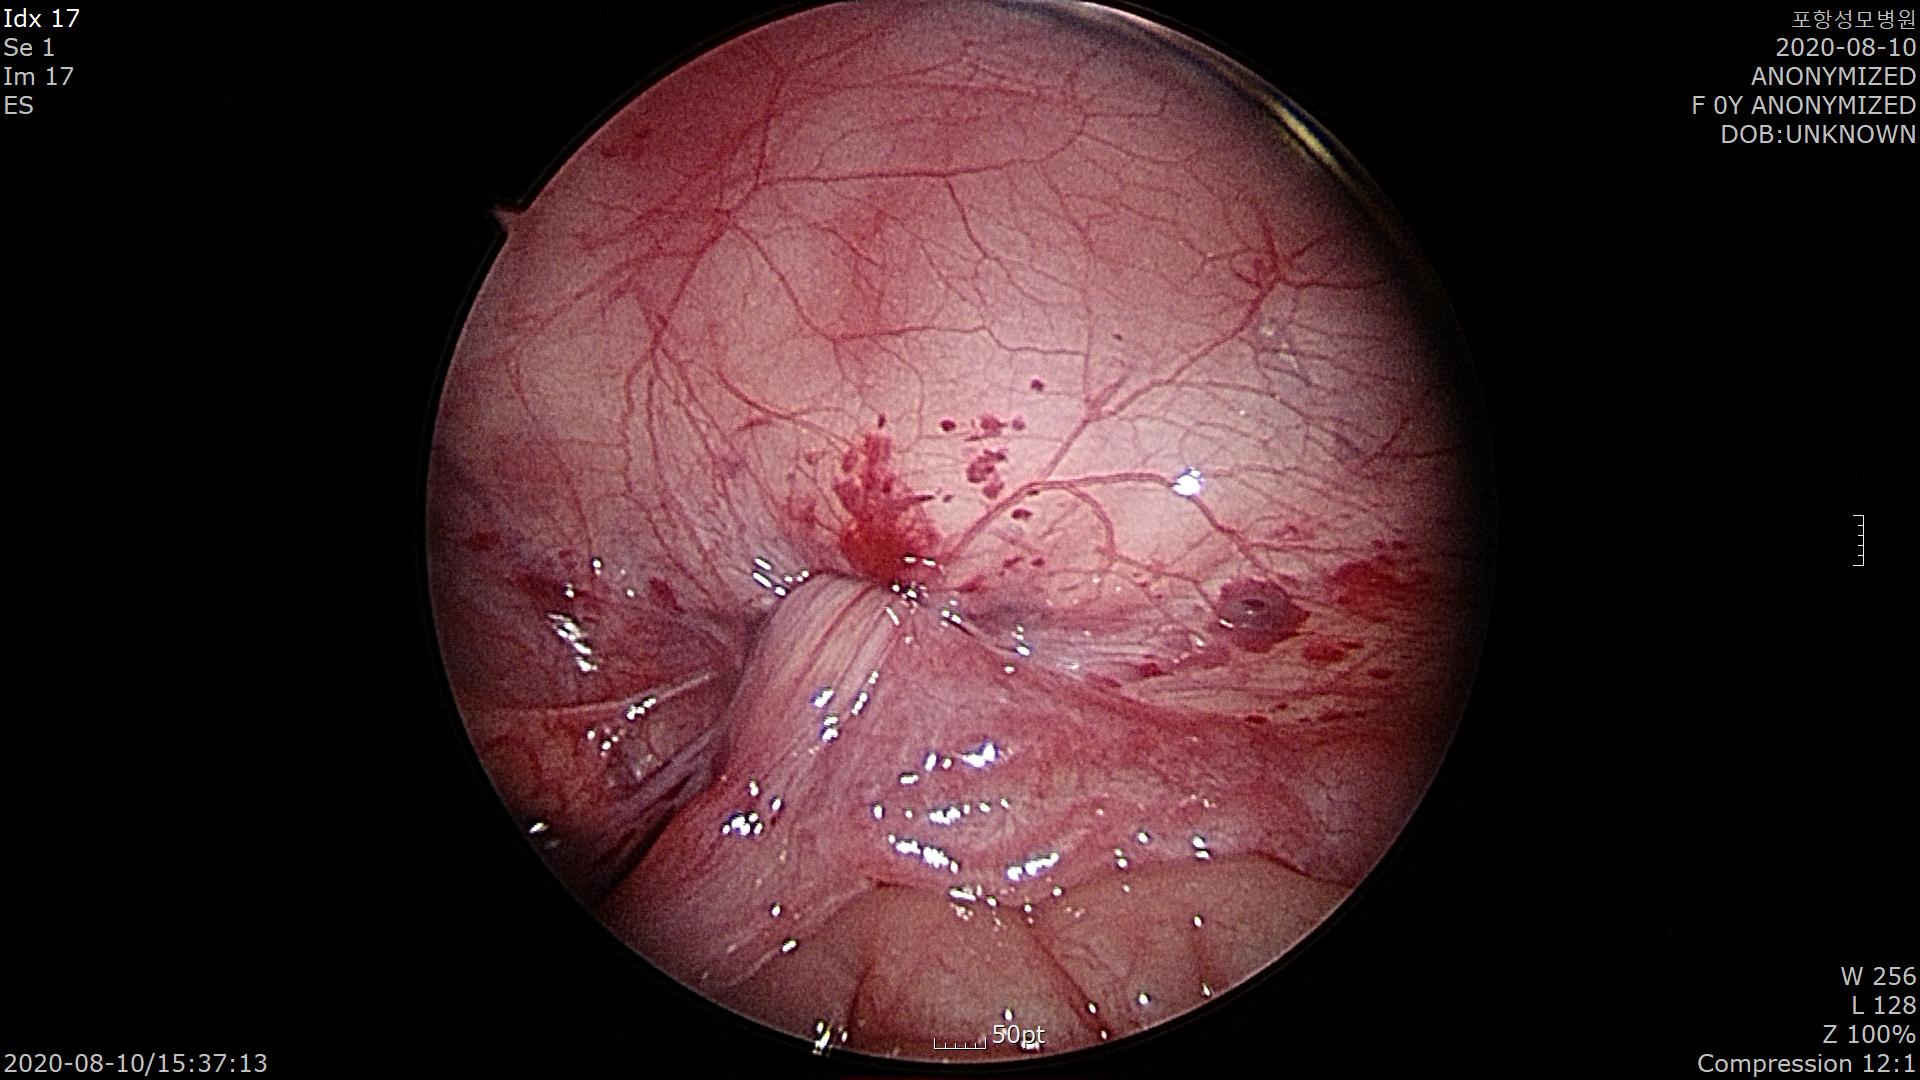

Laparoscpic needle assisted repair기법으로 내서혜륜(Internal inguinal ring)을 봉합해 줍니다.

우측 난소가 약간 부어있지만 혈류는 잘 유지되어 괴사까지 진행하지는 않았습니다.

정말 다행입니다.